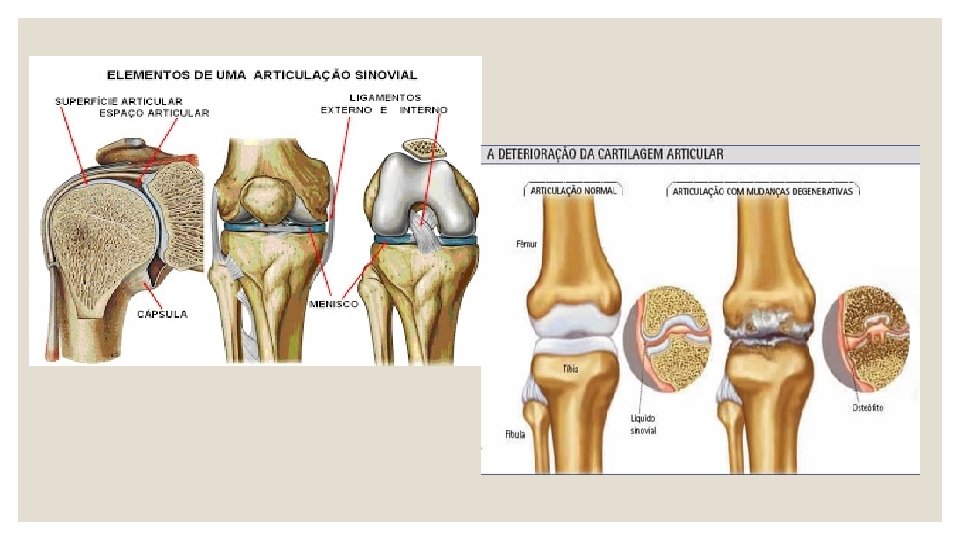

Articulações sinoviais, também chamadas de diartroses ou móveis ◦ Apresenta uma cápsula cheia de líquido sinovial (que funciona como um lubrificante); ◦ Permitem vários tipos de movimento; ◦ Essas articulações possuem uma maior liberdade de movimento e são as mais encontradas em nosso corpo. ◦ As extremidades dos ossos se encaixam e são revestidas por cartilagem. Ex. : Ombro e Joelho e cotovelos. *As bolsas sinoviais atuam como amortecedores em articulações móveis. O líquido sinovial é viscoso, transparente e facilita os deslocamento entre duas partes ósseas. Com o envelhecimento, a produção desse líquido diminui, ocasionando dores nas articulações.

Tipo encaixe ou Articulação em bola Tipo dobradiça Permite a movimentação em vários sentidos, a cabeça de um osso desliza na cavidade do outro. Ex. : articulação do braço com o ombro. Permite movimentos para frente e para trás. Ex. : articulação do Joelho.

LIGAMENTOS ◦ As ARTICULAÇÕES MÓVEIS se mantém UNIDAS por LIGAMENTOS (mantém os ossos próximos, mas com possibilidade de movimentos);

Cartilagem (amortecedor nas articulações)

MEMBRANA SINOVIAL ◦ Membrana interna, FINA que reveste uma articulação móvel; ◦ Secreta LÍQUIDO SINOVIAL; ◦ Função de NUTRIR e LUBRIFICAR as cartilagens (reduzindo o atrito e desgaste na articulação);